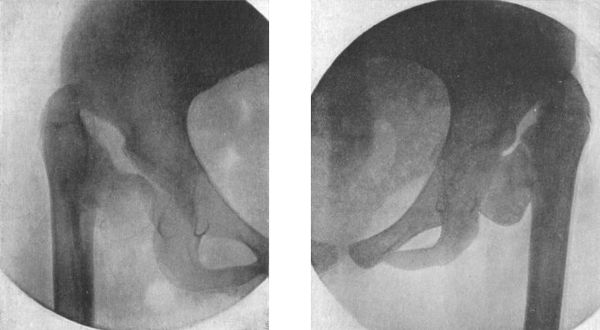

| 72. | Dislocation of Right Femur on to Dorsum Ilii | 143 |

| 73. | Dislocation on to Dorsum Ilii | 144 |

| 74. | Dislocation into the Vicinity of the Ischiatic Notch | 145 |